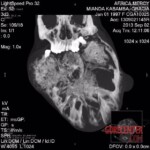

DEMOCRATIC REPUBLIC OF CONGO A 17-year-old girl had been growing a tumour on her face for almost 10 years. It’s grown to the size of a soccer ball. When she and her mother tried to seek medical help at home, the doctors were unable to help her and always sent her home.

By the end, the girl was barely able to eat or speak. Her mother had to watch her suffer. But eventually a Christian pastor helped the girl. He got her medical help from experts in Europe.